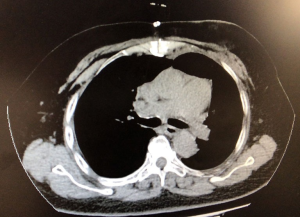

A 68-year-old woman was admitted to our department on September 20, 2019, with complaints of chest tightness and shortness of breath for more than 2 years, with chest tightness and shortness of breath being worse than before. The right upper limb and lower back were also in pain, but the patient was in good mental health. The patient had no history of fever, cough, hemoptysis, significant weight loss, or other symptoms. This patient has a 20 years of history of hypertension with blood pressure up to 180/110 mmHg, but her blood pressure was already under control. Other past medical history includes obsessive-compulsive disorder and cerebral infarction for 15 years. The patient’s personal and family medical history was unremarkable. The physical examination showed the trachea being slightly to the right, no chest deformity, normal respiratory motility, solid sound on percussion of left lung, and clear lung breathing at the auscultation of the right lung field. Her laboratory findings showed no significant abnormality. The chest X-ray result demonstrated a giant mediastinal tumor (Figure 1A). An enhanced chest computed tomography (CT) scan revealed a large mass of 20 cm × 10 cm × 8 cm in size in the anterior mediastinum, invading the pericardium and extending into the bilateral thoracic cavity and causing a mediastinal shift and lung collapse. Most of the mass showed fat density on the CT scan, the CT value was about −56 HU, and the anterior part of the mass was solid while the CT value was about 20 HU. A small amount of liquid was seen in the pericardial cavity, as shown in the figure (Figure 1B). The chest radiology specialists believed that the mass shown in the CT scan might be a mediastinal liposarcoma.